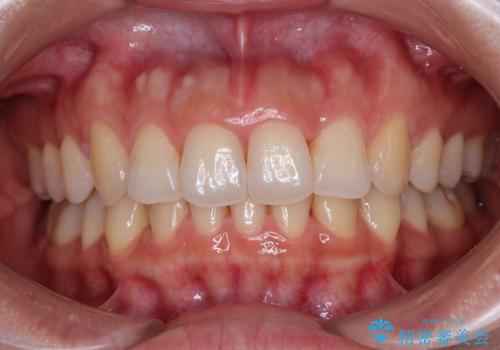

[ 前歯のねじれ・がたつき ] マウスピース矯正

![[ 前歯のねじれ・がたつき ] マウスピース矯正の症例 治療前](https://seimitsushinbi.jp/wp/wp-content/uploads/2024/02/4007c6479f6bce11863dcdd32ed5e39b-500x350.jpg?v=1708502552)

![[ 前歯のねじれ・がたつき ] マウスピース矯正の症例 治療後](https://seimitsushinbi.jp/wp/wp-content/uploads/2024/02/e7a01485e4f4dd0da04705fde4cc34cc-500x350.jpg?v=1708502585)

インビザライン モニター治療 前歯のねじれをまっすぐに